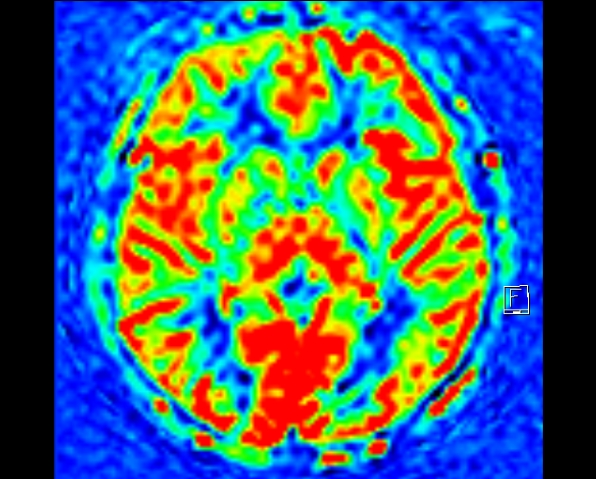

加做 ASL 血流灌注显示左额叶病灶区局部灌注异常,呈稍高信号。

头颅 MRI 高分辨及功能成像:可用于进一步观察细微结构,也可利用功能成像,如,ASL 观察组织血流灌注情况,且无需静脉注射造影剂;MRS 可以敏感地测定局部脑区重要的代谢物浓度,从而反映病灶的病理改变,如 NAA 峰值降低提示神经元数目减少,Cr 和 Cho 峰值升高提示胶质增生。